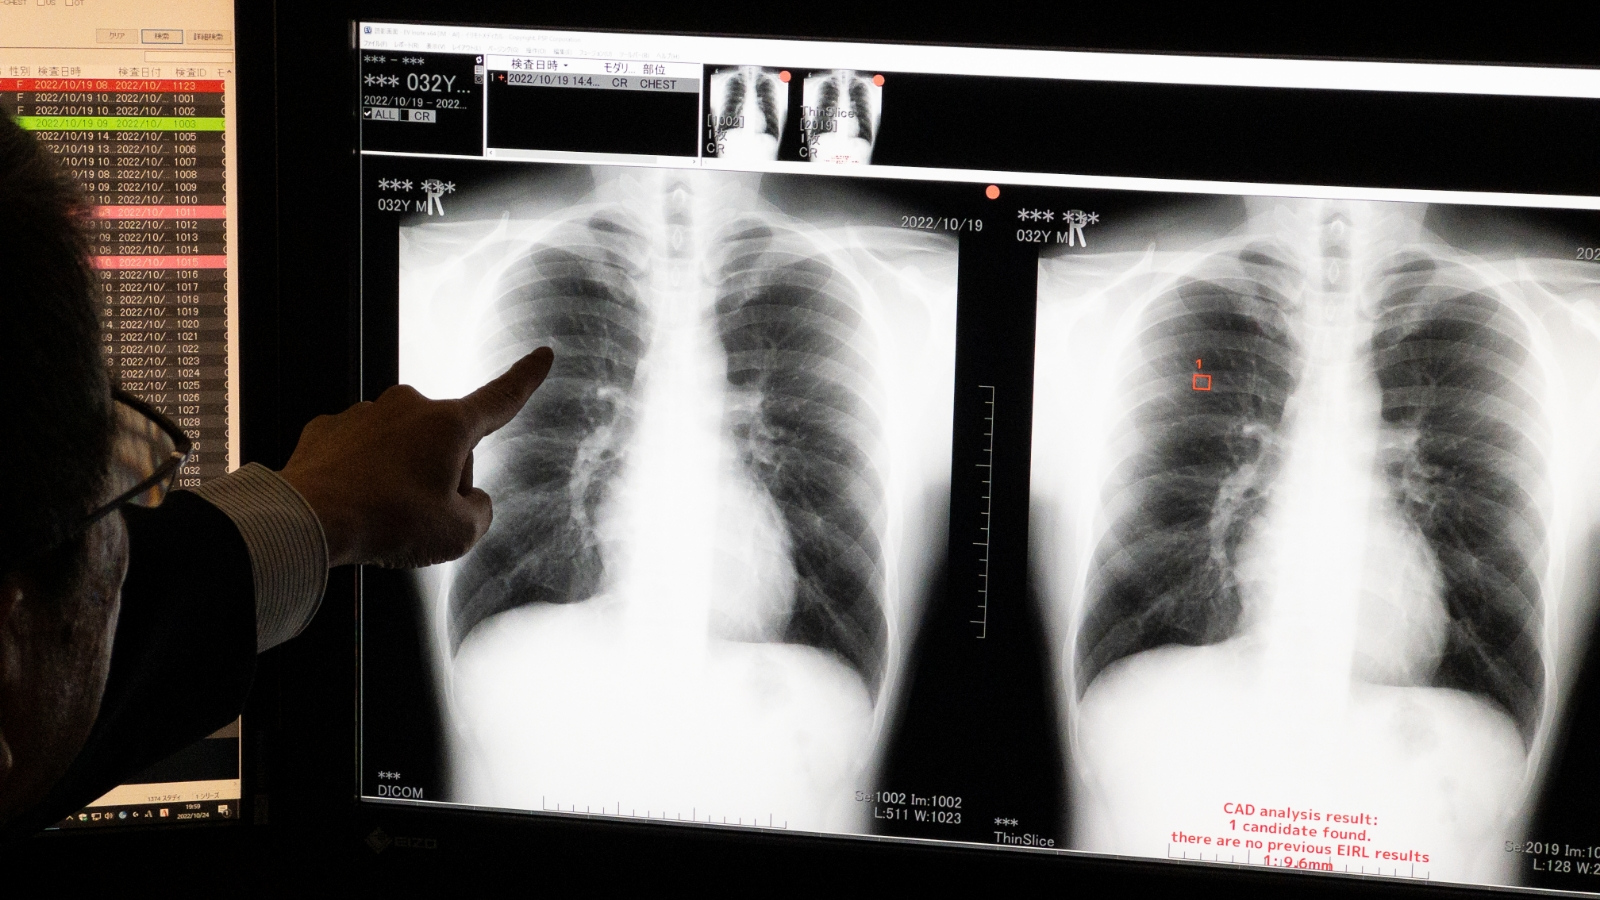

AIを活用して、肺がんの可能性がある部分を読影

DNPは、資本業務提携したイリモトメディカルと共同して、肺がんの可能性がある結節影候補域を検出する「AI支援胸部がん検診読影システム」の運用を2023年3月に開始。読影する医師の負担を軽減し、画像診断の質の向上と効率化を進めます。